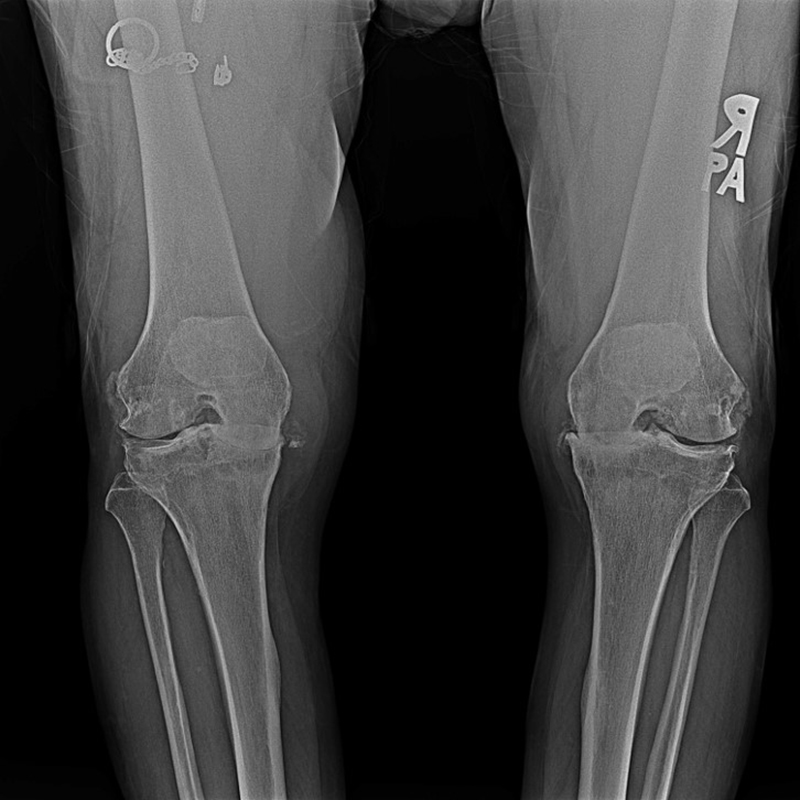

傳統全膝關節置換 首頁 案例分享 膝關節手術 傳統全膝關節置換 江女士 61歲 術前 術後 劉先生 83歲 術前 術後 70歲 柯先生 術前 術後 75歲 黃女士 術前 術後 77歲 羅女士 術前 術後